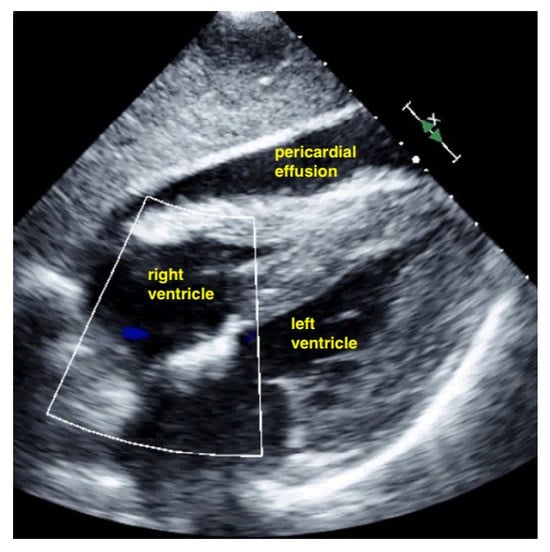

Figure 9.

Pericardial effusion in apical four chamber view compresses the right atrium slightly (RA = right atrium, LA = left atrium, RV = right ventricle, LV = left ventricle).

Figure 10.

Pericardial effusion in subxiphoidal view compresses the right ventricle.